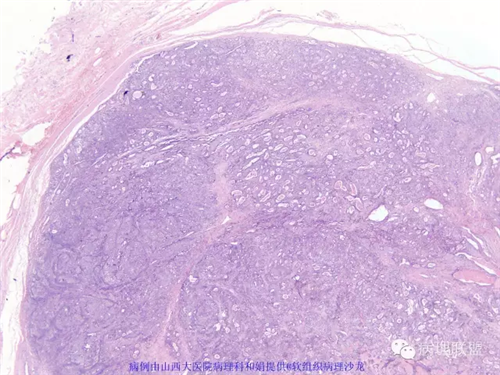

M,57岁,右膝关节外侧皮下肿物10余年,活动度好。

本例形态学上是非常典型的双相型滑膜肉瘤,滑膜肉瘤临床上大部分表现为生长缓慢的肿瘤。以青壮年多见,主要发生于四肢大关节附近,也可见于其他少见部位,如肺、肾等实质器官,形态学分为5种类型:单相纤维型、单相上皮型、双相型、低分化梭形细胞型和小细胞型。有文献报道个别患者有长达20年的病史。